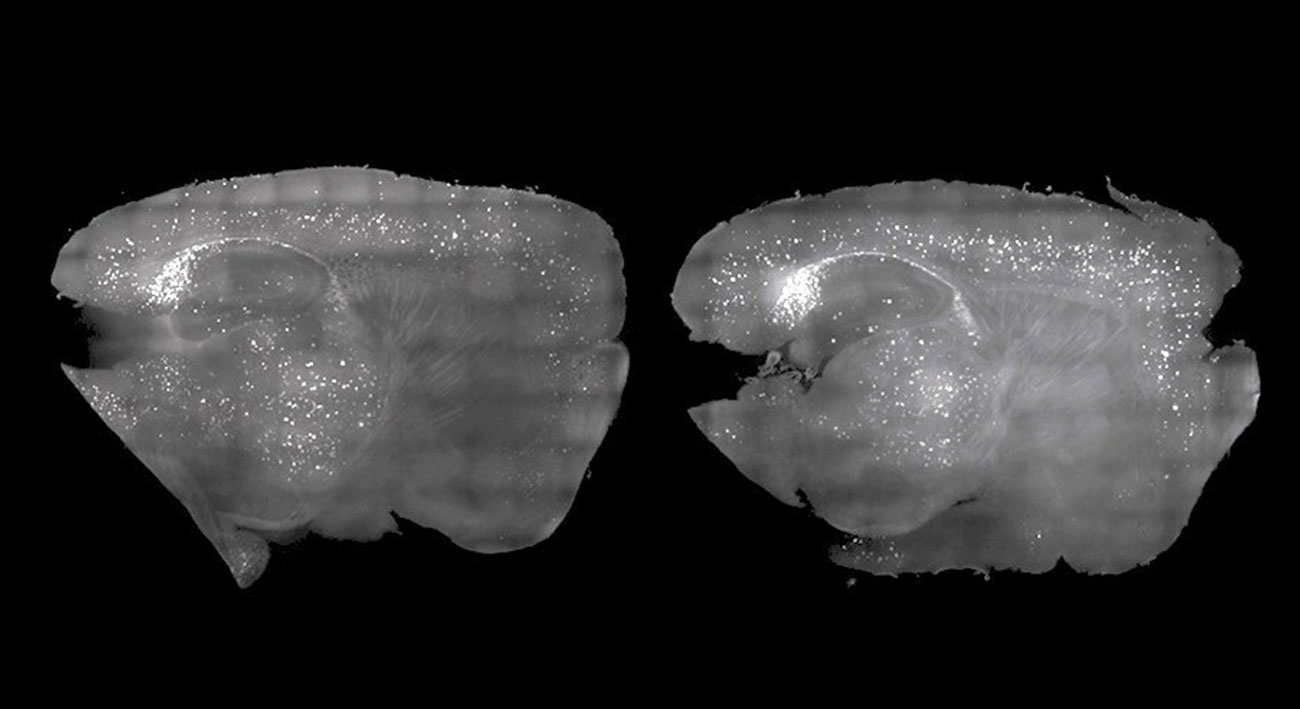

Амилоидные бляшки, которые мешают работе мозга мышей, удалили с помощью звуков. В будущем эти опыты могут привести к появлению дешевого и безлекарственного способа лечения нескольких форм деменции.

Исследования, проведенные в MIT, показали, что стробоскопические лампы и низкочастотное жужжание можно использовать для воссоздания мозговых волн, потерянных при болезни. Также этот метод позволяет удалить часть амилоидных бляшек, которые могут образоваться в мозгу.

Гамма-волны прекращаются или замедляются при некоторых болезнях — например, у людей с Альцгеймером. Вспышки света и низкое жужжание же могут индуцировать гамма-колебания в мозге, уничтожая амилоидные бляшки в его префронтальной коре. В MIT отметили, что мыши, после этих процедур, значительно лучше справлялись с несколькими когнитивными задачами.